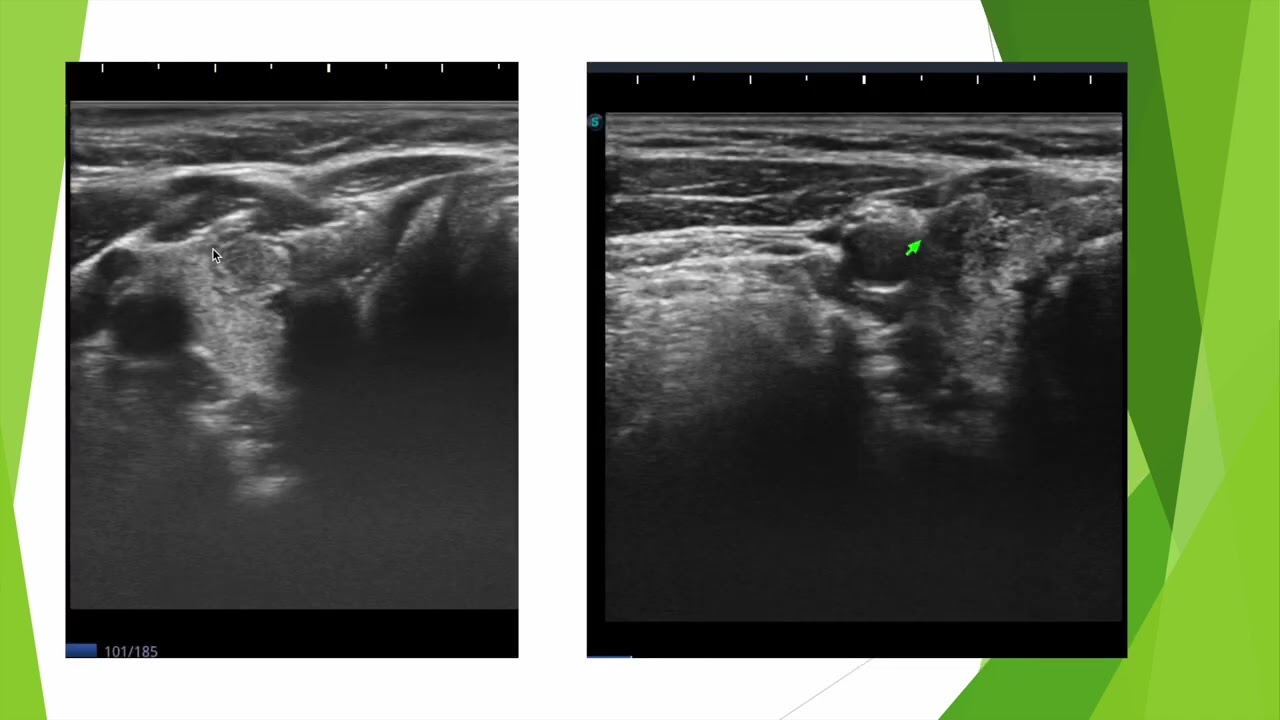

Aspect typique d'une thyroidite autoimmune de Hashimoto en échographie chez une femme de 56 ans. Anticorps anti thyroglobuline positifs et anticorps anti TPO négatifs.